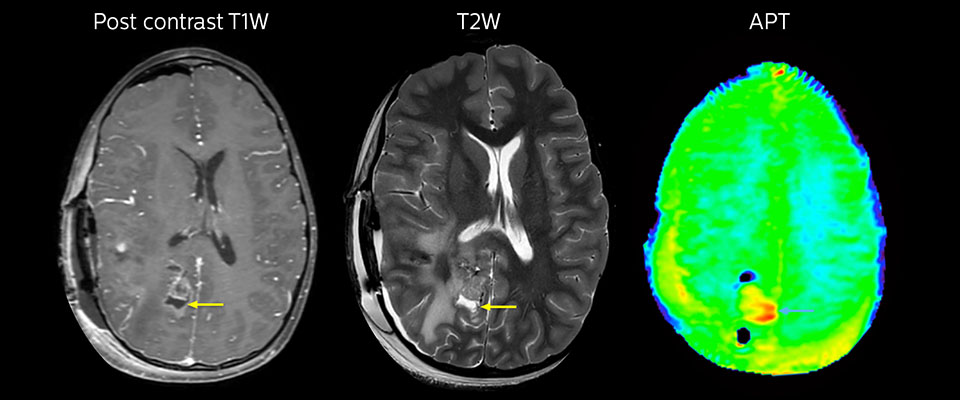

MRI may be performed after tumor resection, to look for residual tumor or tumor regrowth. Also here, the different contrast mechanism of APT may help in diagnosis. Dr. Miller remembers a particular case. “After a very good resection, we saw small changes on the postcontrast T1-weighted and the T2-weighted images that looked like a post-surgical little bit of fluid. Interestingly, however, we saw a focal area of APT signal, right in the center of that abnormality. As we usually do when a bit unsure, we followed it up and, unfortunately, found tumor regrowth in that region,” Dr. Miller says. “Cases like this motivate me, and others who care about this population, to investigate how this APT method could be used on large scale in this population and help us in providing high value diagnostic information.” The hospital’s physicians also saw a case where APT had a negative predictive value. Following the resection of a highgrade tumor, they saw a similar small change in the images of this patient. However in this case, the APT signal was rather low. In a recent rescanning of this patient, no recurrence was seen.